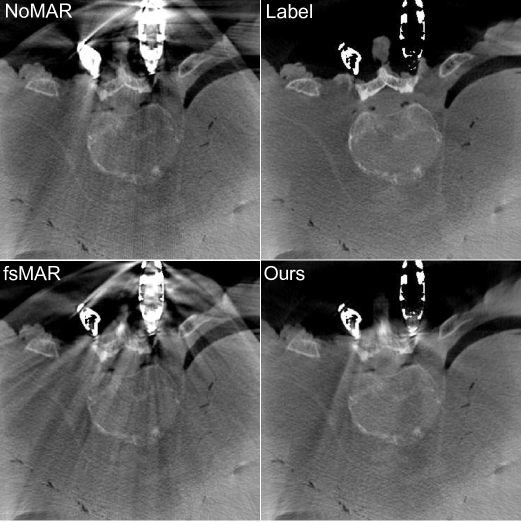

Figure 8: Overview about the per-slice SSIM scores and one slice (marked as a gray dotted line) of each of the corresponding reconstructions for the first 5 TS of the first fold. Each row comprises the quantitative (left) and qualitative (right) results of one test scan. The 1st column of the qualitative results shows the label reconstructions, the 2nd column shows the reconstructions without the use of a MAR method (NoMAR), the 3rd column shows the reconstruction using the standard fsMAR method and the 4th column shows the corresponding reconstruction of using our proposed segmentation method for the modified fsMAR (Ours). The red outlines represent the envelope of the joint segmentation masks which are used to mask the metrics’ scores. All regions inside the denoted envelope are set to 00 during the metric calculations. All shown reconstructions are windowed with [500, 2048] HU.

Refer to caption

By examining the qualitative results and the corresponding SSIM line plots presented in Fig. 8 illustrating the results for test scans 1 to 5 and Fig. 9 illustrating the results for test scans 6 to 11 of the first fold, similar effects can be observed. It becomes apparent that for the majority of test cases the standard fsMAR, as well as the modified fsMAR, perform equally well, with a slight beneficial tendency for the proposed approach. The differences are that marginal, that they do not visually show up in the corresponding presented slices (cf. Fig. 8 & Fig. 9). This especially holds for scans comprising knees. However, investigating the qualitative results for test scans 2, 3 (Fig. 8), 6, 8, 9 (Fig. 9) and the example in Fig. 10, significant differences can be observed. In Fig. 8 at test scan 3 comprising a spine, it can be seen that the standard fsMAR is not able to segment the complete inserted pedicle screws, but only the associated heads. Due to that, only artifacts originating from the screws’ heads are reduced, whereas present beam hardening artifacts at the tips of the screws remain unchanged. In opposition to that, the proposed approach shows reduced artifacts throughout the complete size of the screws. Similar effects can be observed for test scans 8 and 9 in Fig. 9 where the segmentation of the standard fsMAR misses parts of the screws. For test scan 2 (Fig. 8) it becomes apparent that the streak artifacts, which originate from parts of K-wires, which lie outside the FoV of the reconstruction, are reduced more efficiently using the proposed segmentation approach. The represented slice for test scan 6 (Fig. 9) shows a similar case in which metal reaches from outside the FoV into the reconstruction. Whereas the standard fsMAR is able to fully segment the present metal plate and only an insufficient part of the metal lying outside and at the border of the volume, the modified fsMAR segments all present metal parts, thus achieving a more artifact reduced reconstruction. For both cases, a significant performance difference can also be seen in the corresponding line plots. However, similar to the quantitative results, the most significant difference between the two approaches can be seen for the presented test scan in Fig. 10. While for the shown slice, the standard fsMAR is not able to reduce any of the artifacts due to a failed segmentation, our approach nearly completely removes the present artifacts. Furthermore, the superior performance is not only reached in the single presented slice but rather holds for the complete set of slices.